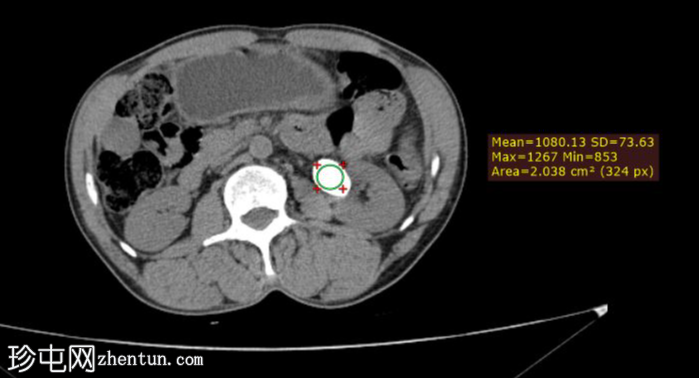

轴位结石

5.png

密度

测量结石密度是CT检查在治疗方案制定中的主要原则。

对于我们的患者,肾盂结石密度大于1000亨氏单位(HU)适合采用体外冲击波碎石术。相反,密度小于 1000 HU 的肾下极结石或肾盂结石是经皮肾镜取石术 (PCNL) 的候选对象。